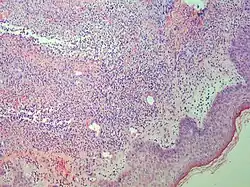

| Dermatitis herpetiformis |

|

| Early febrile neutrophilic dermatosis (Sweet's syndrome) | Neutrophilic and lymphohistiocytic infiltrate and edema.[27] |